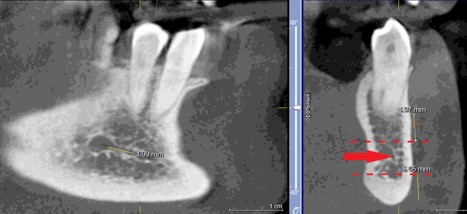

Данные осложнения происходят из-за повреждения резцовой петли – внутрикостного продолжения нижнелуночкого нерва (Рис. 1a и 1b), которая начинается от ментального отверстия и заканчивается индивидуально, как правило, на уровне латерального или центрального резца [1].

Рисунок 1а: КЛКТ. Панорамный реформат.

(Зеленая стрелка – резцовая петля, красная стрелка – подбородочное отверстие.)

Рисунок 1b: КЛКТ. Коронарный реформат нижней челюсти в переднем отделе.

(Зеленая стрелка – резцовая петля)